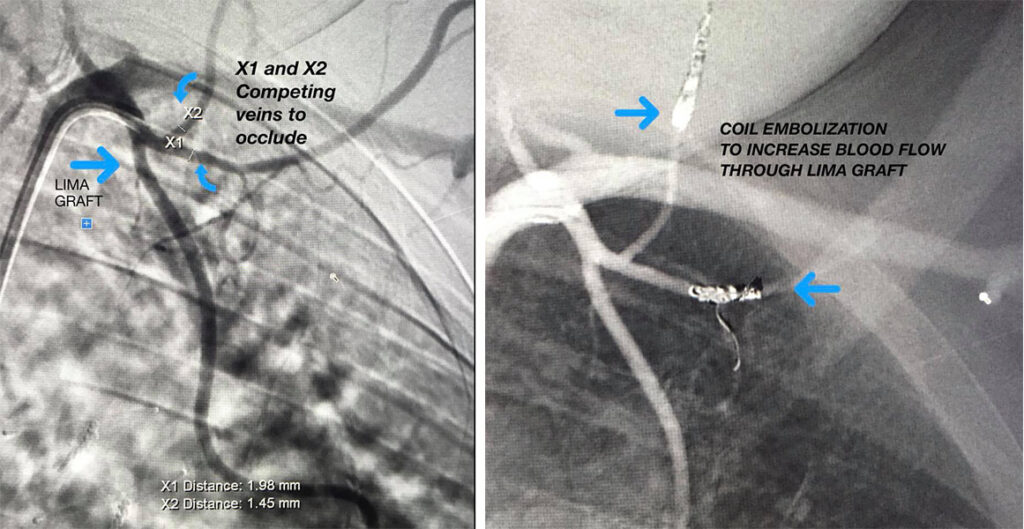

Patient with recurrent chest pain. Patient has had a LIMA Graft placed previously. LIMA- Left Internal Mammary Artery used for CABG - Coronary Artery bypass grafting. Competing arteries can take away blood flow through the LIMA graft. Dr. Meka received this patient and used coil embolization to block off the competing arteries (X1 and X2) and revascularize the LIMA graft by occluding the competing arteries.